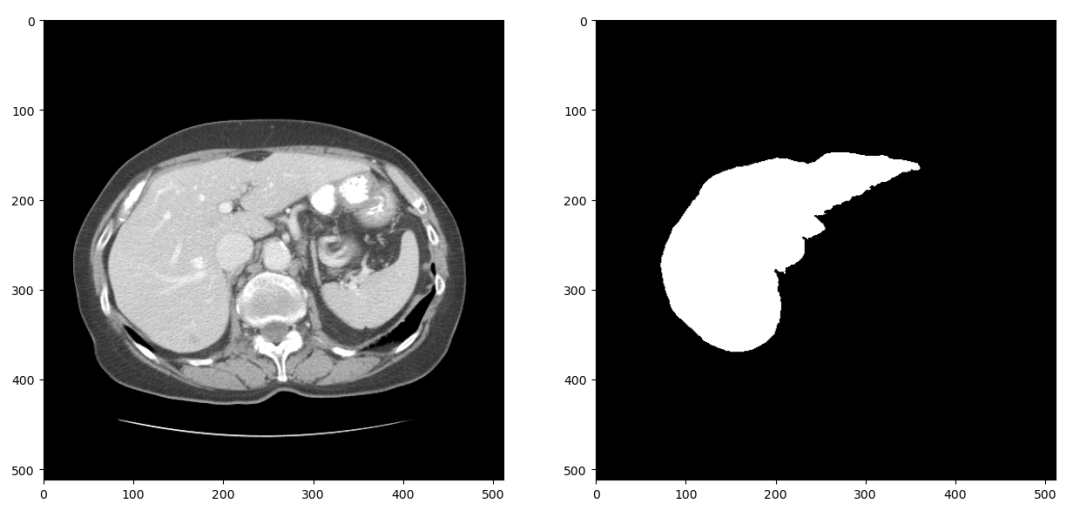

在训练深度神经网络的过程中,我们通常需要在训练集上训练多个epoch以让网络达到一个比较高的训练准确率。但是这样做又容易使网络过拟合训练集,其表现为网络在训练集上准确率很高但是测试时准确率偏低。针对这个问题有多方面的解决方案,数据增强是其中重要的一种。这个项目中我们采用的数据增强策略包括随机水平、垂直翻转、随机旋转、随机尺度缩放、随机位置裁剪和弹性形变。在项目中可以看到具体代码,图5是对图4中数据进行数据增强的结果:

![]()

图5 数据增强效果

CT图像和分割标签共同进行了左右翻转,逆时针15度旋转,0.8倍尺度缩放和弹性形变。虽然一些简单的数据增强步骤过后图像看起来没有很大区别,但是只要图像有变化对算法来说就是新的数据,结合Droupout、权重正则化等方法能较好地抑制网络过拟合,提升测试准确率。